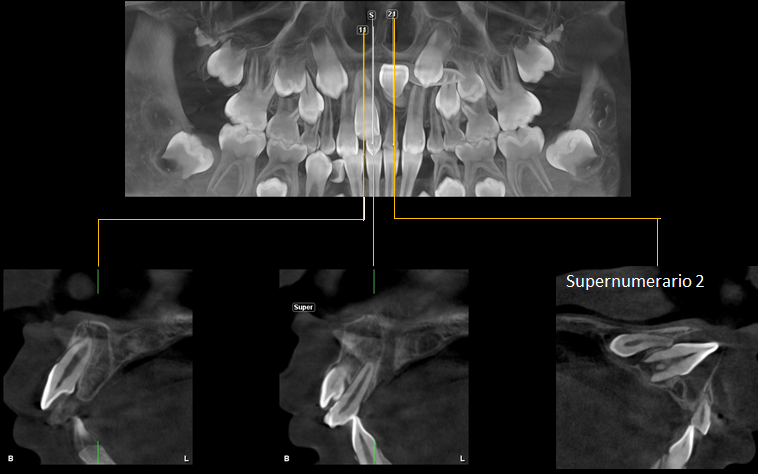

A la evaluación de la tomografía computarizada se puede observar con más claridad el supernumerario denominado “A” de forma rudimentaria que se encuentra por palatino de la pieza 11 y que contacto con la cortical del agujero nasopalatino, asimismo observamos la pieza 21 con la porción coronaria en contacto con la tabla ósea vestibular adelgazándola; finalmente y como hallazgo imagenológico se encontró un segundo supernumerario denominado “B” que se localiza cefálico a la pieza 21 también en posición transversal pero con la porción coronaria en contacto con la tabla ósea palatina y el piso de fosa nasal y finalmente el tercio apical se e en contacto con

la región cervical de la pieza 21.

CORTES TRANSAXIALES